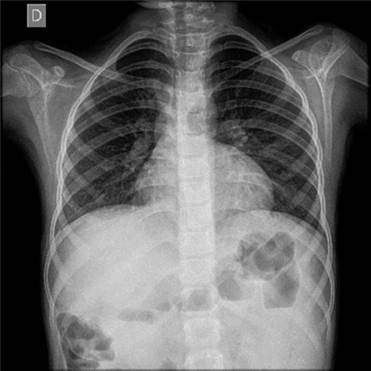

La radiografía de tórax resultó normal (Figura 1). La tomografía axial computarizada (TAC) de tórax demostró un incremento en la vasculatura pulmonar hiliar (Figura 2). Las pruebas de espirometría resultaron con valores normales del predicho: relación VEF1/FVC de 88%, VEF1 de 84% y FVC de 84% y la pletismografía sin alteración. 1

La radiografía de tórax se describe como normal en los pacientes con síndrome hepatopulmonar12,13. La TAC de tórax está indicada para excluir anormalidades en el parénquima pulmonar que causen hipoxemia14. Se puede observar la presencia de dilataciones vasculares4, como las encontradas en este caso.